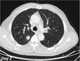

Immunodeficiency, also known as immunocompromisation, is a state in which the immune system's ability to fight infectious diseases and cancer is compromised or entirely absent. Most cases are acquired ("secondary") due to extrinsic factors that affect the patient's immune system. [Source: Wikipedia ]